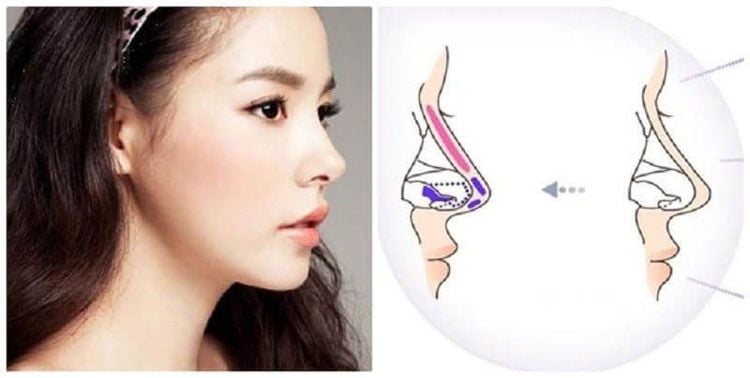

- Sụn hyaline (sụn mũi): Còn được gọi là sụn khớp, sụn hyalin tạo thành một lớp dày trên các đầu xương trong khớp. Là loại phổ biến nhất trong cơ thể. Sụn hyalin cũng được tìm thấy trong xương sườn, vách ngăn của mũi ngăn cách lỗ mũi và ống thở (khí quản), thanh quả và xương sườn.

- Sụn đàn hồi (sụn tai): Sụn đàn hồi chủ yếu được tạo thành từ các sợi protein elastin giúp nó linh hoạt hơn, cung cấp sức mạnh và độ đàn hồi cho các cơ quan và cấu trúc cơ thể. Sụn được tìm thấy ở tai ngoài, một phần của mũi và thanh quản.

Kỹ thuật sửa mũi bọc sụn này cần hai bước. Đầu tiên, bác sĩ lấy một mảnh sụn khỏe mạnh của một người và gửi mẫu sụn đó đến phòng thí nghiệm. Trong phòng thí nghiệm, các tế bào sẽ được “nuôi cấy” và kích thích để phát triển.Sau đó, người này đi phẫu thuật, nơi sụn bị hư hỏng được loại bỏ và thay thế bằng sụn mới phát triển. Một bác sĩ phẫu thuật cũng đã thực hiện các sửa chữa khác. Bởi vì phương pháp này yêu cầu nhiều thủ tục phẫu thuật, các bác sĩ thường chỉ thực hiện trên những người trẻ hơn bị thương tích từ 2 cm trở lên.